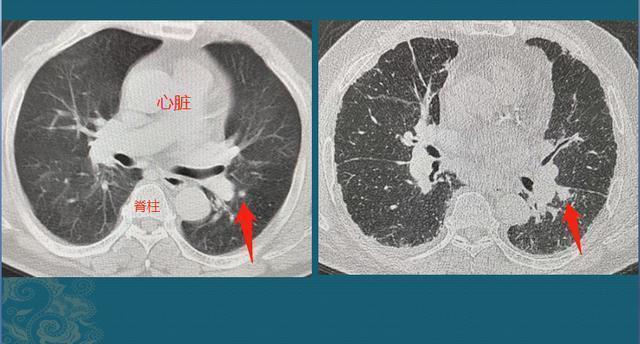

上图这位老年男性患者,因为头晕住院,胸部体检发现左下肺实性小结节,直径5mm,建议他3-6个月复查,结果老人的家属没有遵从指导,直到18个月后,老人出现胸痛、咳嗽症状才回来复查,结节增大到1.1cm,由于位置靠近叶间胸膜,癌细胞顺着胸膜上丰富的脉管系统转移了,没有根治机会了……肺腺癌的转移时机也不一致,有些病人肿瘤增大到5cm以上仍然没发生转移,依旧有手术机会。所以癌症病人的运气,其实也很重要!肺结节的平均生长速度上面分别介绍了肺腺癌的3种生长方式,它们的增殖速度并不相同,不同病人身上也有差异。有文献统计了一个平均值,供大家参考一下: